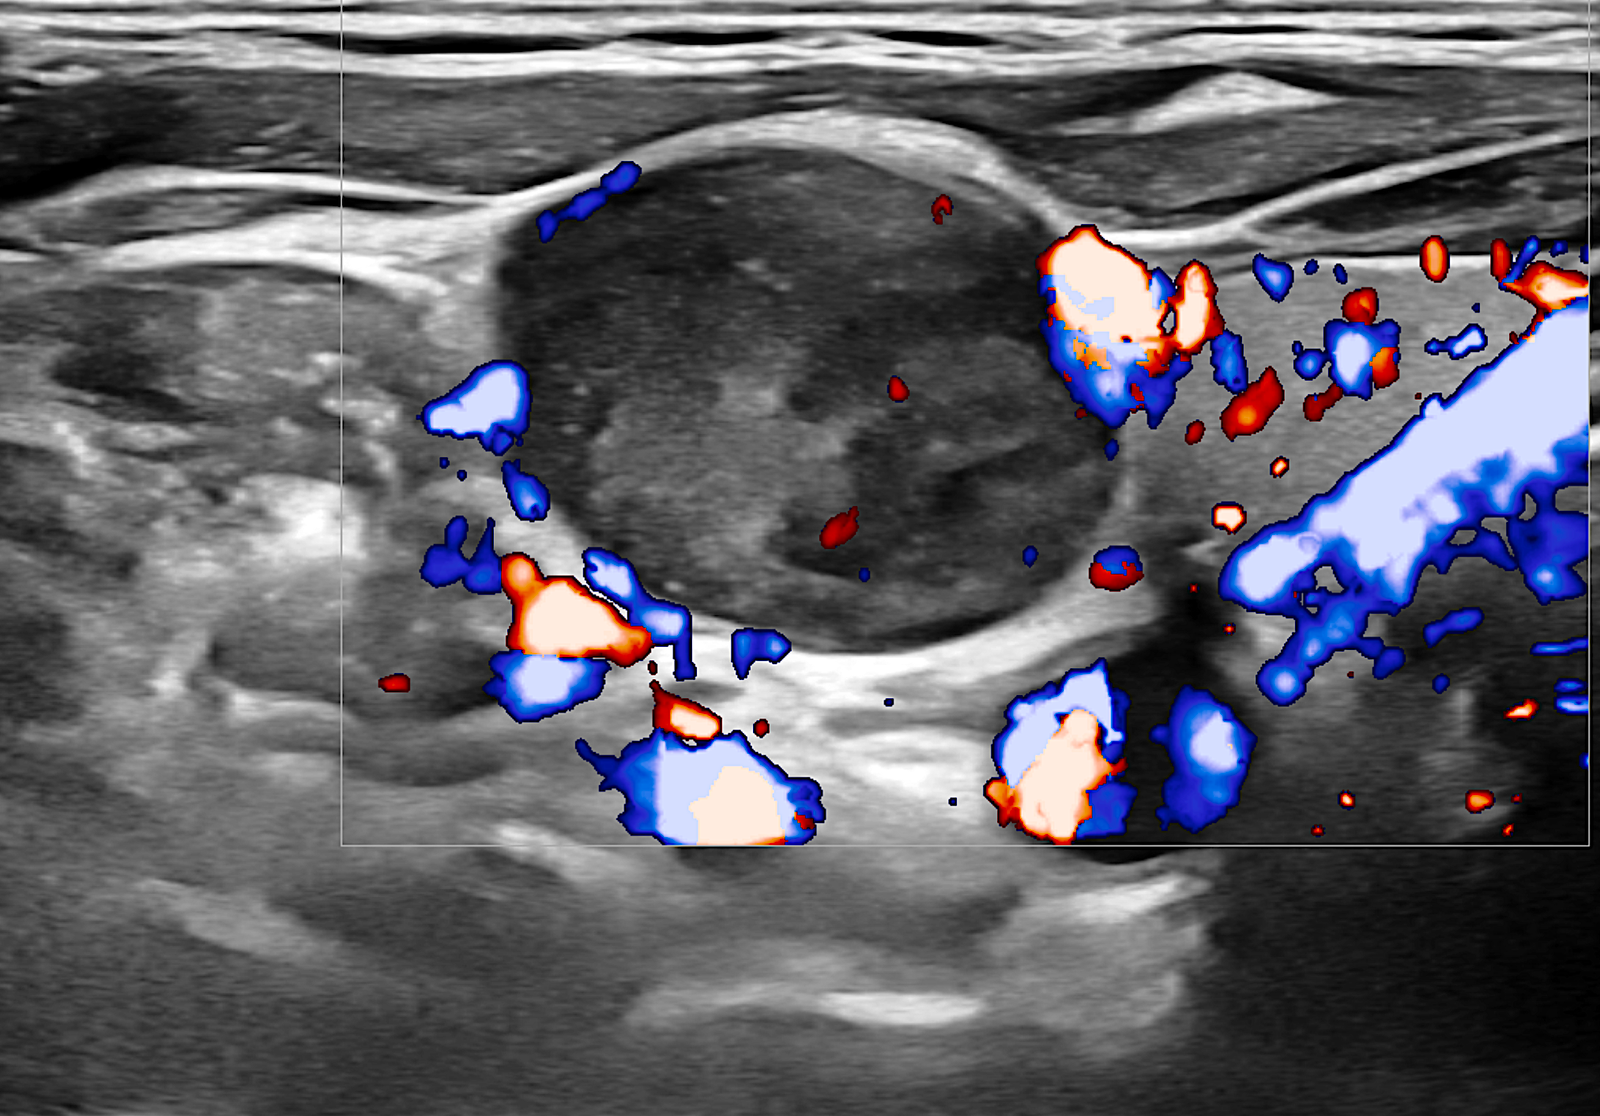

Παραγαγγλίωμα Τραχήλου